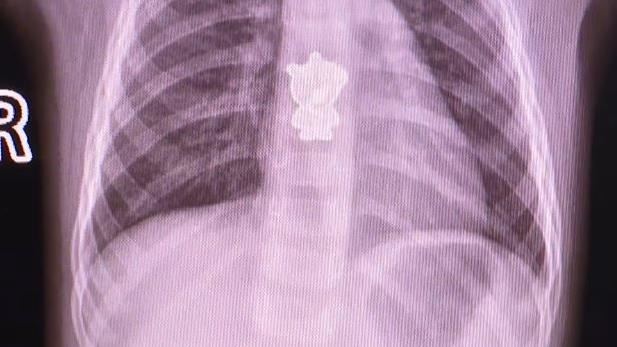

小孩子喜歡把物品塞嘴巴裡,家長務必要隨時緊盯,以免吞下異物造成窒息。中國湖南長沙

一名1歲女童起床後哭鬧不止,咳嗽時竟然還「帶血」嚇壞了家長,趕緊送往醫院檢查,醫

生替女童做電腦斷層掃描(CT),竟然發現在食道下方有一隻卡通角色「佩佩豬」。

根據《新浪新聞》報導,來自湖南長沙的1歲女童,起床後就開始哭鬧不止,家長一直找不

到原因,直到女童開始咳嗽,甚至咳出血絲,才驚覺不妙立刻將她送醫。濟南省兒童醫院耳

鼻咽喉頭頸外科主治醫師王敏替她拍攝電腦斷層掃描,發現在食道中下段發現了一個明顯的

異物,仔細一看竟是卡通角色「佩佩豬」。

▲醫師進行手術取出一枚金屬佩佩豬。(圖/翻攝自騰訊新聞)

醫師進行手術後將其取出,才發現是一個佩佩豬的金屬裝飾,被女童不慎吞下了肚。媽媽表

示,那是一個鞋子上的裝飾品,可能本來就不牢固,被女兒拔下來拿在手上把玩,沒想到會